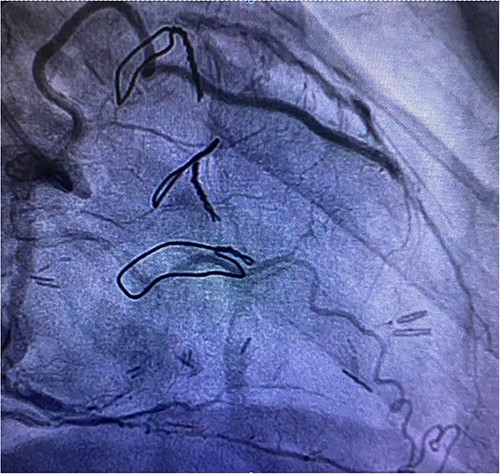

Before resternotomy, a cardiopulmonary bypass was performed via the right common femoral artery and vein. The RIMA was harvested in a semi-skeletonized fashion because skeletonized IMA is in general, longer than pedicled IMA. However, the RIMA could not reach the LAD in the present case due to cardiomegaly. Therefore, the proximal end of the RIMA was cut to use as a free graft. Subsequently, the proximal portion of the patent RA graft was tried to dissect as a proximal anastomosis site, but it was not possible due to severe adhesion of the surrounding tissue. Therefore, we decided to anastomose the proximal RIMA to the proximal right coronary artery (RCA) as the inflow site. The distal RIMA was anastomosed to the LAD as usual (Fig. 1). The postoperative course was uneventful, and the patient was discharged 11 days after the operation. A 3-month postoperative coronary angiogram showed the patency of the RA and RIMA conduits (Fig. 2). Moreover, from coronary computed tomography angiography after 6 years, it was confirmed that it was still patent (Fig. 3).

The free RIMA was anastomosed to the mid-part of RCA and bypassed to the distal LAD.